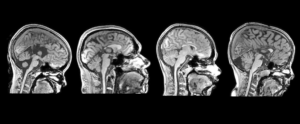

Os pesquisadores reuniram um grupo de 12 participantes: um grupo com 6 indivíduos sem alterações cerebrais e outro grupo com 6 indivíduos com DCC. Os participantes foram submetidos a um exame de ressonância magnética funcional para investigar quais regiões cerebrais estão encarregadas do processamento somestésico na DCC. Durante blocos de estimulação, um estímulo tátil cutâneo indolor foi aplicado com uma escova macia na palma da mão dos voluntários.